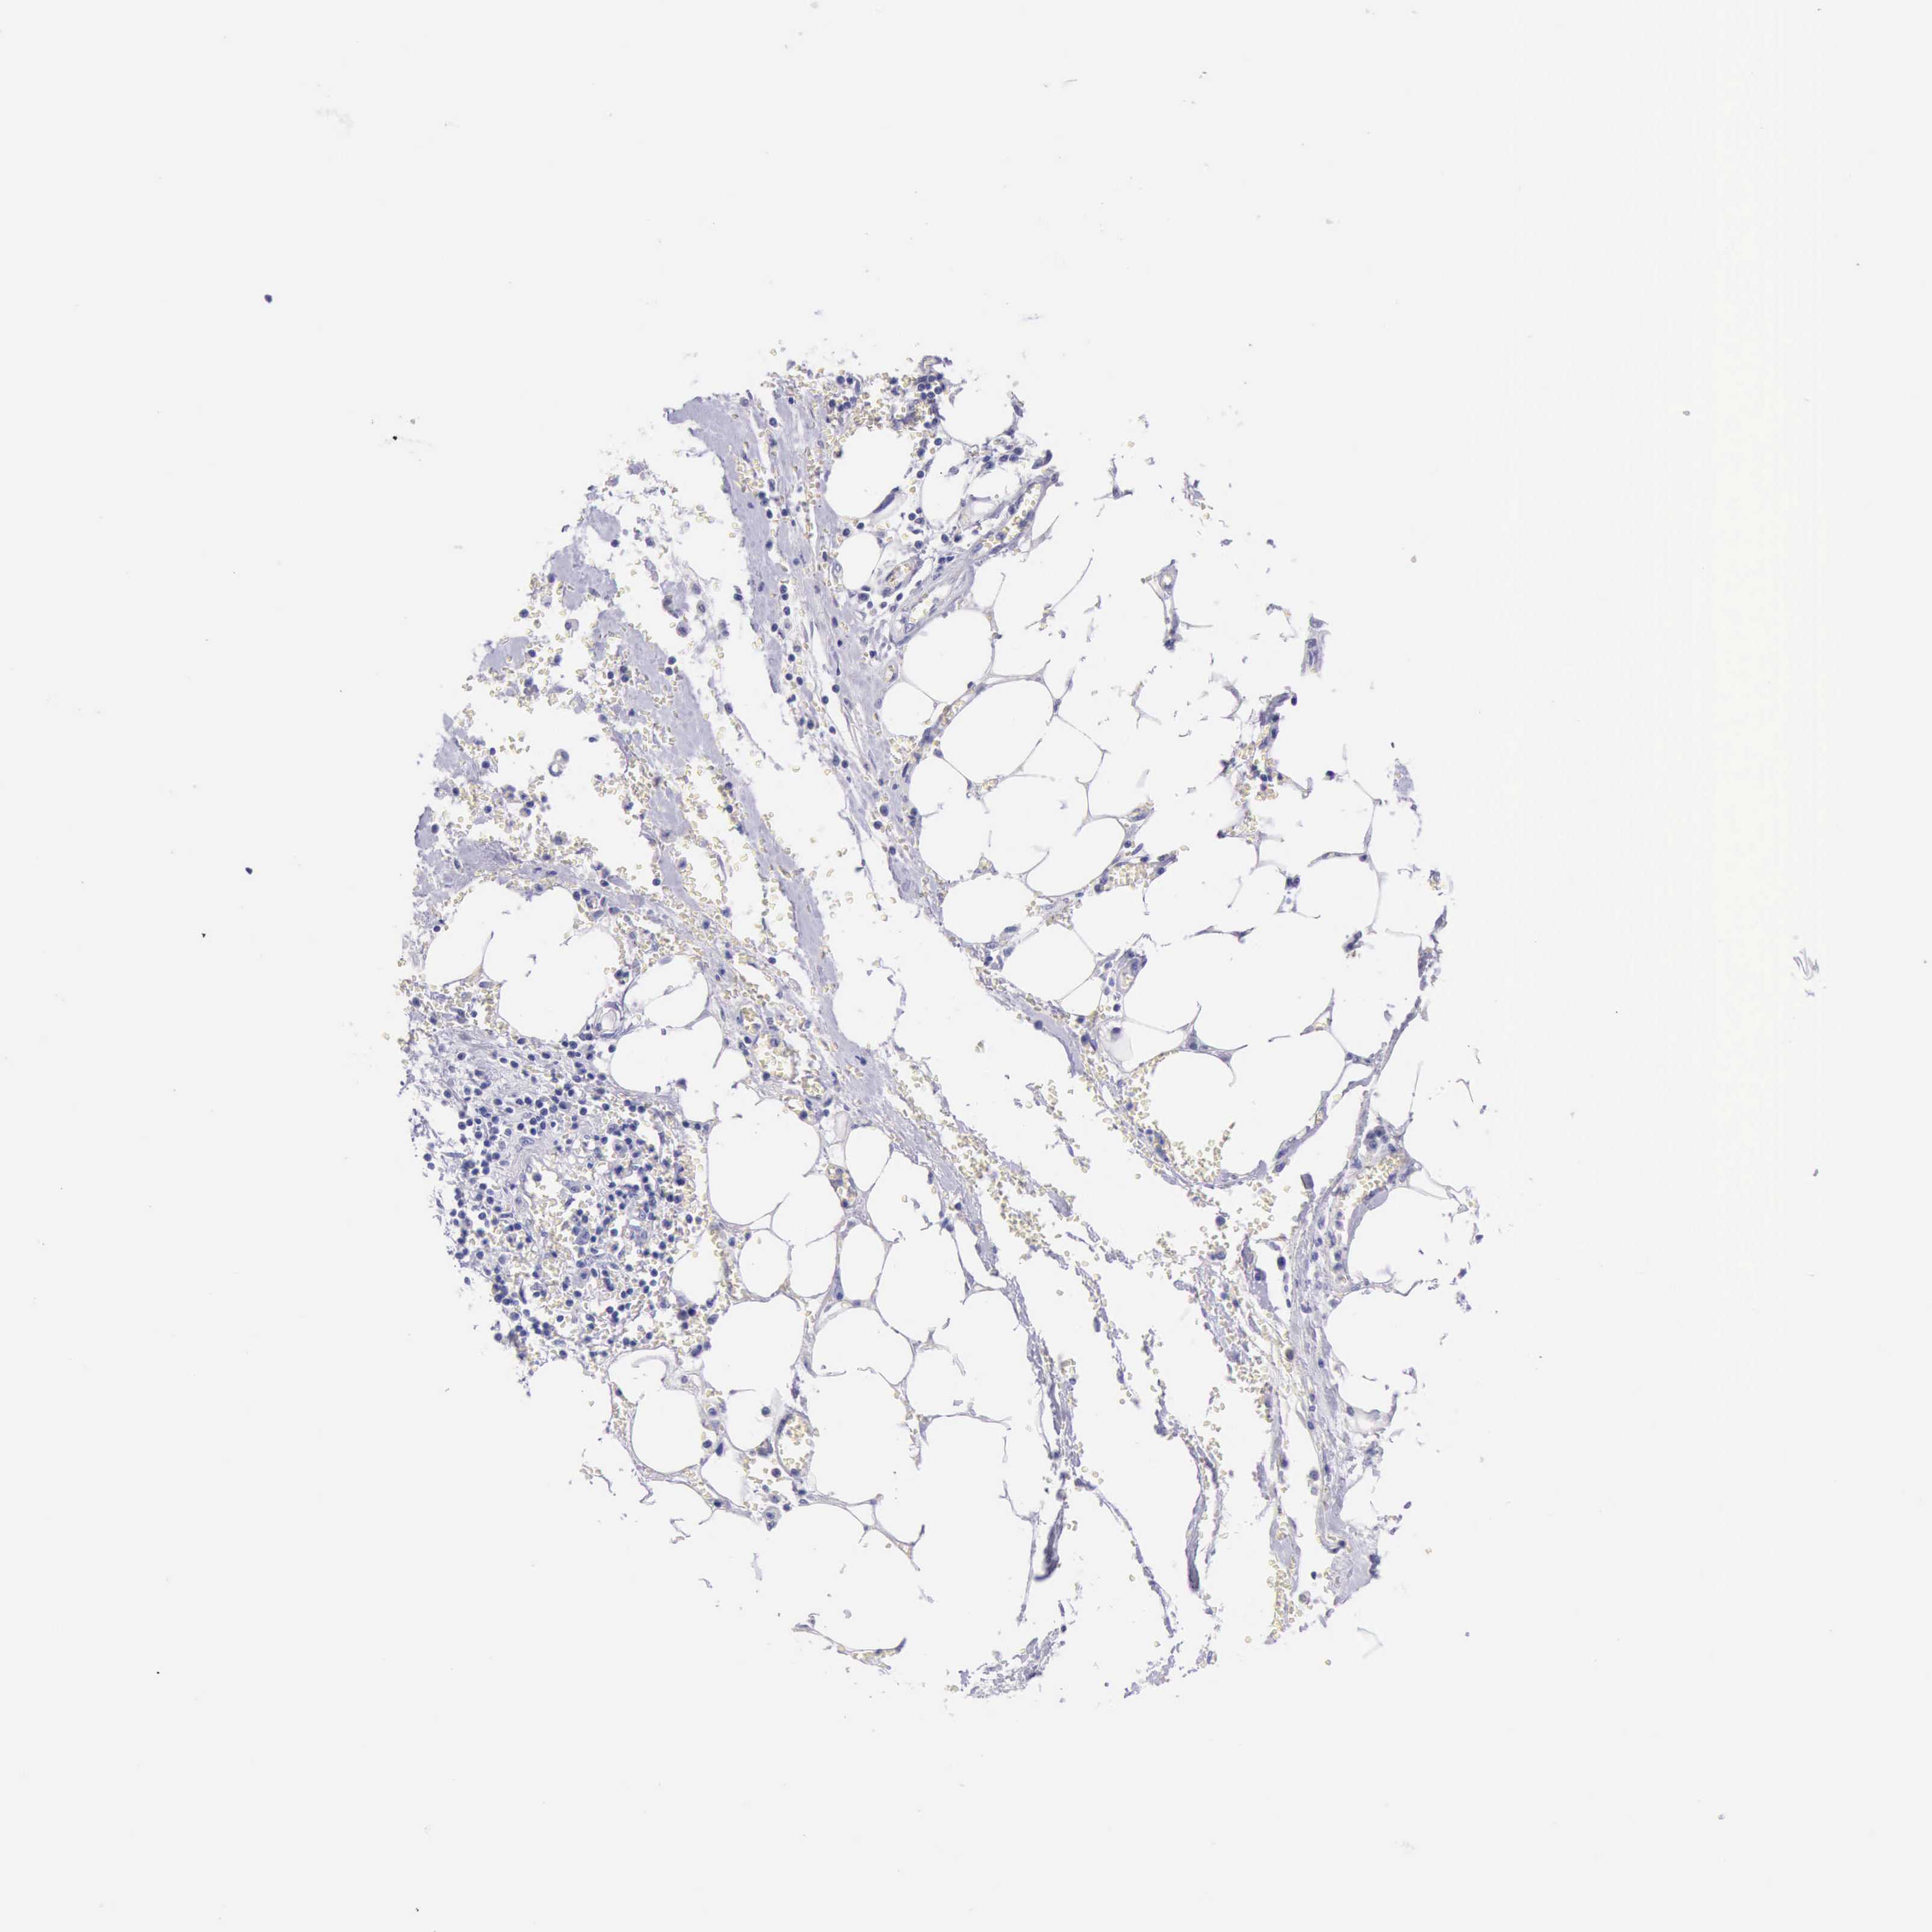

PANCREATIC CANCER - Protein expressioni

A mouse-over function shows sample information and annotation data. Click on an image to view it in a full screen mode. Samples can be filtered based on level of antibody staining by selecting one or several of the following categories: high, medium, low and not detected. The assay and annotation is described here.

Note that samples used for immunohistochemistry by the Human Protein Atlas do not correspond to samples in the TCGA dataset.

Antibody stainingi

Antibody staining in the annotated cell types in the current human tissue is reported as not detected, low, medium, or high, based on conventional immunohistochemistry profiling in selected tissues. This score is based on the combination of the staining intensity and fraction of stained cells.

Each image is clickable and will lead to virtual microscopy that enables deeper exploration of all samples and also displays staining intensity scores, fraction scores and subcellular localization as well as patient and tissue information for each sample.

Antibody HPA001177

Staining

High

Medium

Low

Not detected

Intensity

Strong

Moderate

Weak

Negative

Quantity

>75%

75%-25%

<25%

None

Location

Nuclear

Cytoplasmic/membranous

Cytoplasmic/membranous,nuclear

Adenocarcinoma, NOS